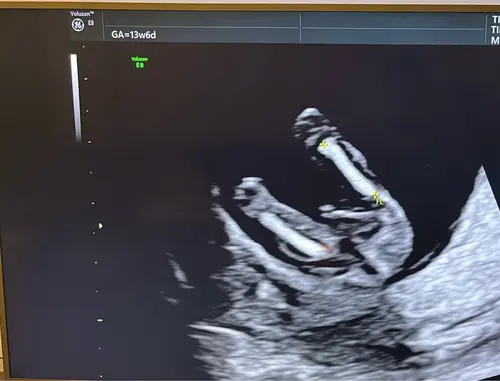

Ik vind het zo knap dat mensen hier wijs uit komen, ik kom er zelf maar niet uit, maar ben stiekem ook wel benieuwd of onze 2de een jongen of meisje is, kan iemand helpen? 😊

Alvast bedankt !

Wellicht dat ik hier tussen kom haha.. ziet iemand wat het is?😂